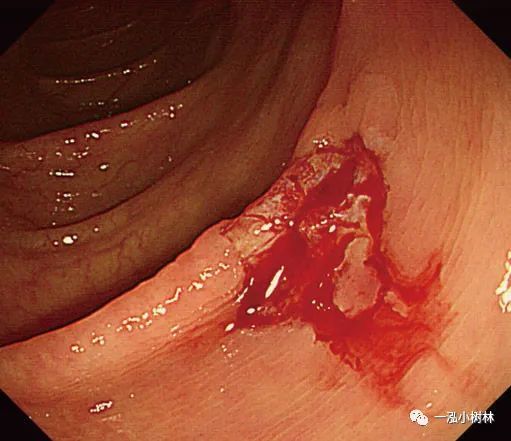

图1c 小息肉切除瘢痕,5年后腺瘤复发

图1d NBI观察